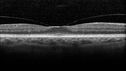

Vitreomacular traction OU - Aborted in 3 months - Right eye initial visit375 views62 year old female with blurred vision in both eyes for 2 months intermittently. She was referred for macular edema.

A 20/32 OD, 20/25 OS

OCT showed VMT in one eye and edema in the other

3 months later in the last 2 OCT scans

VA 20/20 OD, 20/16 OS and VMT had released.     (0 votes)